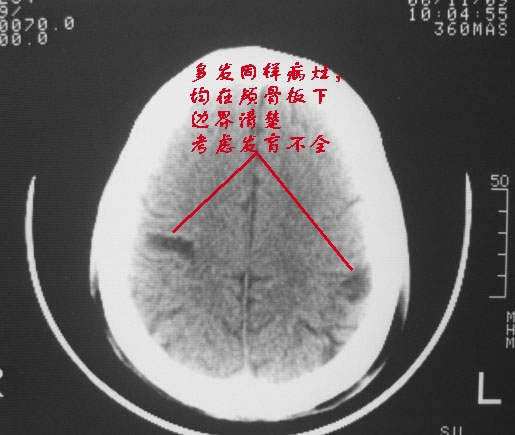

以下是引用dyqct在2006-11-9 15:04:00的发言:[br]左枕叶、双顶叶各见一处似三角形低密度区,边界尚清楚,无占位效应,累及皮质,白质侧未见灰质影。余所见未见异常。[br]考虑:1、脑软化灶;[br] 2、不支持脑裂畸形,该病病变区两侧应有灰质带——即灰质异位,临床上常有顽固性颠痫。当然了脑软化灶也偶会出现颠痫。

以下是引用守望可可西里在2006-11-9 15:06:00的发言:[br][br] 1.左侧枕叶低密度与侧脑室相通,考虑开唇型脑裂畸形。[br] 2.双侧顶叶低密度考虑局部脑沟异常扩大,发育问题。